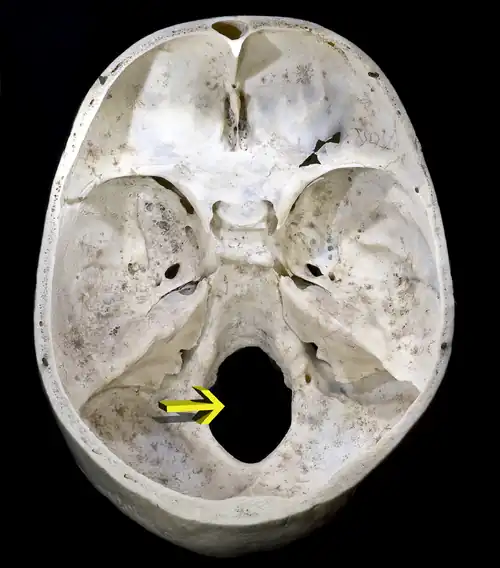

Vue interne d'un occipital humain.

Foramen magnum.

Face interne

On décrit sur la face interne :

Ces sillons délimitent deux fosses cérébelleuses et deux fosses cérébrales.